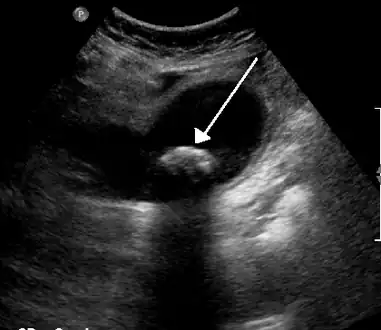

Diagnosis is typically confirmed by abdominal ultrasound. Other imaging techniques used are ERCP and MRCP. Gallstone complications may be detected on blood tests.[2]

On abdominal ultrasound, sinking gallstones usually have posterior acoustic shadowing. In floating gallstones, reverberation echoes (or comet-tail artifact) is seen instead in a clinical condition called adenomyomatosis. Another sign is wall-echo-shadow (WES) triad (or double-arc shadow) which is also characteristic of gallstones.[38]

A 1.9 cm gallstone impacted in the neck of the gallbladder and leading to cholecystitis as seen on ultrasound. There is 4 mm gall bladder wall thickening.